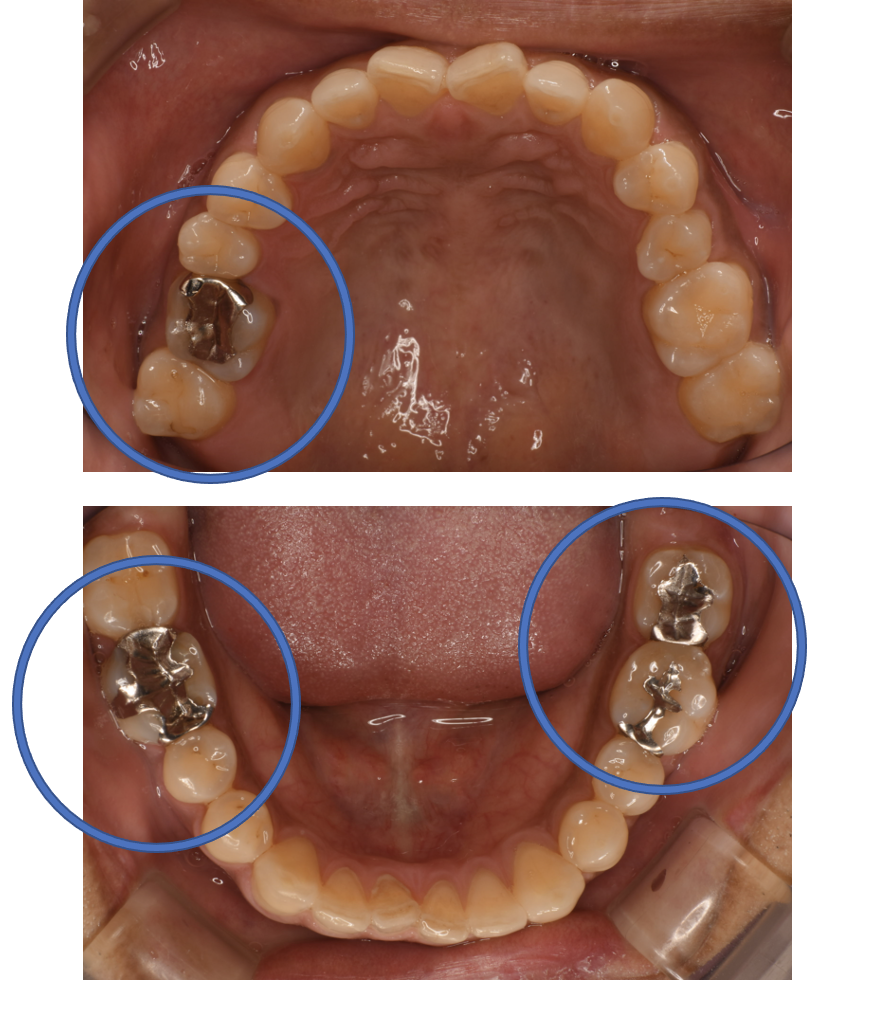

Before

| 備考 | 院長より 銀歯の内部に虫歯が進行してしまっていたケースです。元々、大きい金属が入っている部位は、ジルコニアCrで被せ、比較的小さめの金属が入っていた場所は、セラミックInで詰めて対応したケースです。お口のなかが明るくなりました。 |